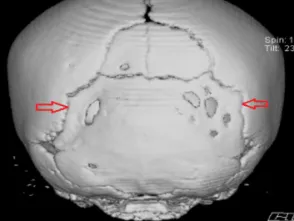

El Síndrome de Apert es una enfermedad de tipo genético catalogada como ¨poco frecuente¨ está clasificado como una anomalía cráneo facial, ya que los bebes que nacen con esta patologías caracterizan por una sutura precoz entre los huesos del cráneo, (craneosinostosis), alteraciones en los huesos y distintos niveles de retraso mental Este síndrome es el resultado de una mutación genética para ser concretos la del gen FGPR2 (factor de crecimiento de fibroblastos) que se da en el cromosoma numero 10.

- Fusión prematura de las fontanelas: esta anomalía en bebes puede producir retraso mental, aunque suele causar el crecimiento longitudinal y estrecho de la cabeza, en lugar de crecer a lo ancho.